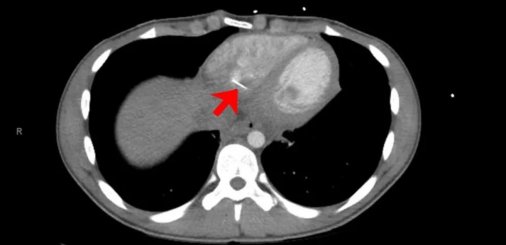

Μια αξονική τομογραφία του στήθους του έδειξε ότι υπήρχε ένα “γραμμικό μεταλλικό ξένο” αντικείμενο στην καρδιά του, ανέφερε η έκθεση. Το αντικείμενο είχε μήκος περίπου 3,5 εκατοστά και έβγαινε από τη δεξιά κοιλία της καρδιάς.